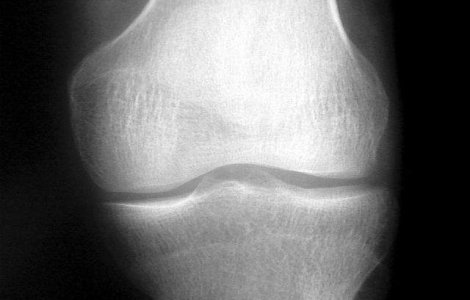

Potrivit studiilor oamenii ai caror parinti au suferit o inlocuire totala a articulatiei unui genunchi din cauza osteoartritei prezinta un risc de peste doua ori mai mare de a suferi de dureri de genunchi la varsta mijlocie, comparativ cu aceia care nu au avut in familie probleme de acest tip.